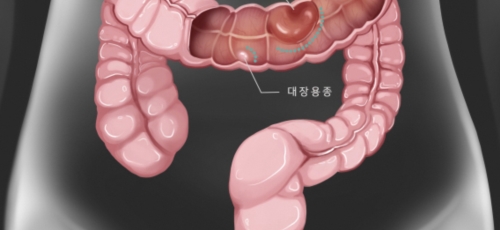

대장암이란?

대장이라는 기관은 우리 몸 소화기관의 마지막에 있는 부위인데요 길이는 1.5m가량 되며, 소장 다음으로 길이가 긴 장기로 대변이 만들어지는 최종 마지막 장기입니다. 암이 결장에 생기면 결장암, 직장에 생기면 직장암이라고 하는데요 이를 통상적으로 대장암이라고 합니다. 즉 대장암이란 결장이나 직장에 생기는 악성 종양으로 대부분이 점막의 샘 세포에 생기는 경우입니다.